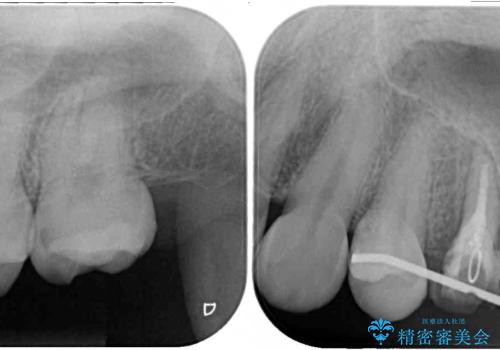

まずは虫歯を除去した上で根管治療を行い、部分矯正により骨内深い位置にまで及んだ健全な部分を引っ張り出すこととしました。

その後骨形成処置を行い、治癒を待って補綴治療を行うこととしました。

かなり深い位置にまで虫歯が及んでいたため、かなりの量を引っ張り出す必要があり、残された歯根は短く小さい状態となりました。

今後も定期的にレントゲンを撮るなど、経過を追っていく必要があります。